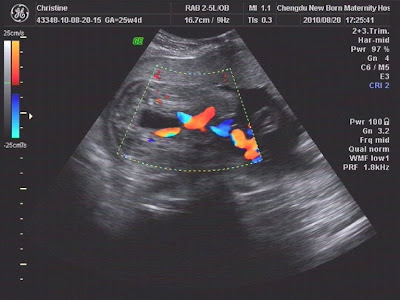

This is a picture of the blood flow in the heart chambers. What's weird to me is they can count/ measure the 4 chambers and then monitor the blood flow but we still have no idea if it's a boy or girl haha!